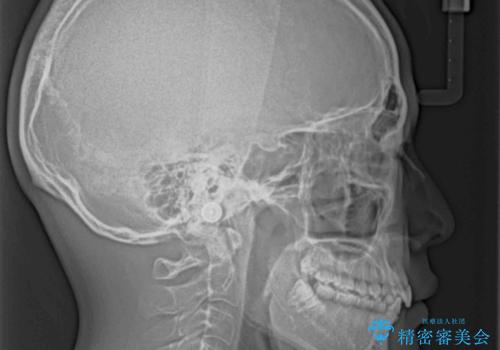

- 上下前歯のデコボコと深い咬み合わせを気にして来院された患者様です。

下顎前歯が一本欠損しており、下顎の歯列が小さいため、ディープバイトになりやすい状態でした。

傾斜しいている大臼歯を立ち上げながら、下顎歯列を上顎に対して前方位となるように工夫し、デコボコを解消した上でディープバイトも改善することができました。